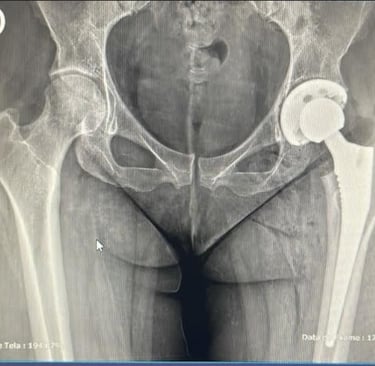

A cirurgia de prótese de quadril é um procedimento médico necessário em casos de artrose avançada, onde a dor intensa e a limitação de movimento comprometem a qualidade de vida dos pacientes. Compreender as dúvidas comuns relacionadas a este procedimento pode ajudar a desmistificar o processo e proporcionar segurança aos que estão prestes a enfrentá-lo.

Um fator que muitos pacientes consideram é a durabilidade da prótese. Em média, as próteses de quadril podem durar mais de 20 anos, dependendo do uso e da condição física do paciente. Essa longevidade faz da cirurgia uma opção viável para aqueles que buscam melhorar a qualidade de vida por um longo prazo.